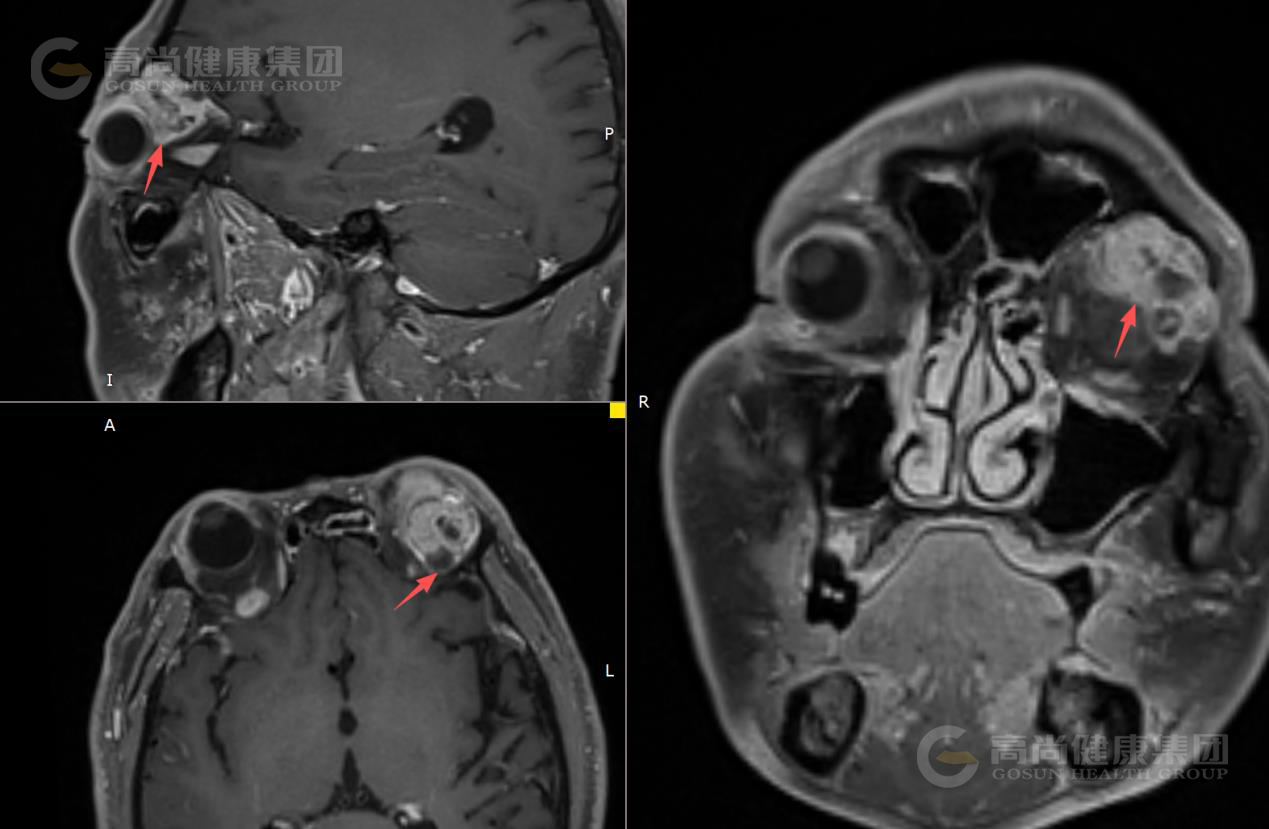

眼眶MR平扫+增强扫描

序列 T1WI T2WI T2WI-FS DWI/ADC T1-VIBE+C 3D-T1WI+C

方位 TRA SAG COR

左眼眶外上泪腺区类圆形异常信号影,大小约23×26×26mm(左右径×前后径×上下径),呈囊实性改,T1WI呈等信号,T2WI及T2WI-FS序列主要呈稍高信号伴囊样高信号,实性部分DWI呈轻度高信号,囊性部分呈等信号,ADC实质部分呈低信号,囊性部分呈高信号。

MR增强扫描: 肿块实质部分呈明显强化,且持续强化,囊变区不强化,病灶累及左眼眶肌锥内外间隙,与邻近泪腺界限不清,左侧眼球受压、向前突出,左侧上直肌、外直肌轻度受压。

影像诊断结果: 左侧泪腺区肿瘤性病变,考虑泪腺混合瘤,部分囊变坏死,不除外其它,请结合临床。